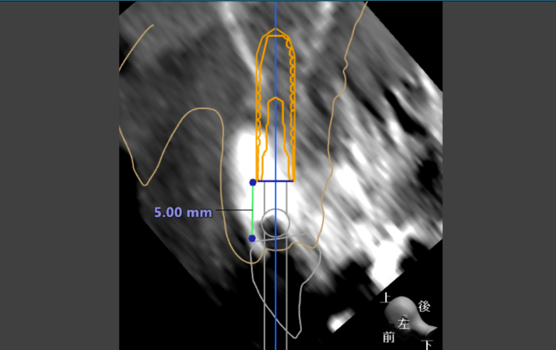

抜歯即時インプラント症例写真

抜歯と同時にインプラント埋入から仮り歯まで入れるので、手術回数が少なく、歯のない期間がないことが最大のメリットとなります。

初診

前歯のブリッジが折れて来院。前歯のインプラントは骨が薄く、多くの場合骨の造成が必要だが、治療期間が長くかかってしまう。そのため、今回はインプラントを骨のあるところに埋入して抜歯即時インプラントを選択した

治療計画をたて、埋入ポジションを正確にするためにステントを作成

同日にインプラント埋入から仮り歯まで作成した。